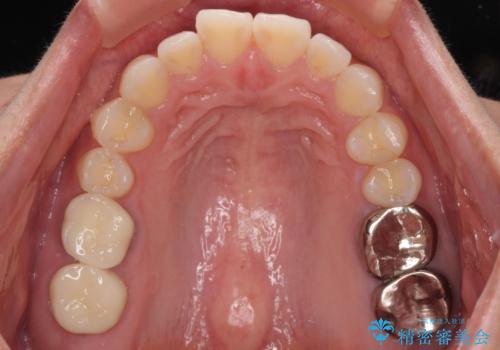

スペースが整った段階で、右下の第一大臼歯と第二大臼歯にインプラントを埋入。

その後、挺出していた右上第一大臼歯と第二大臼歯に装着されていた銀歯についても、審美性と適合性の向上を目的に、オールセラミッククラウンにやり替えました。

これにより、より自然で美しい見た目と、高い精度の咬合が得られています。